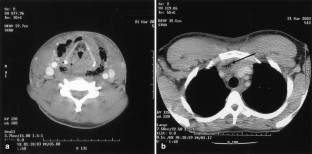

Fig. 2

Fig. 3